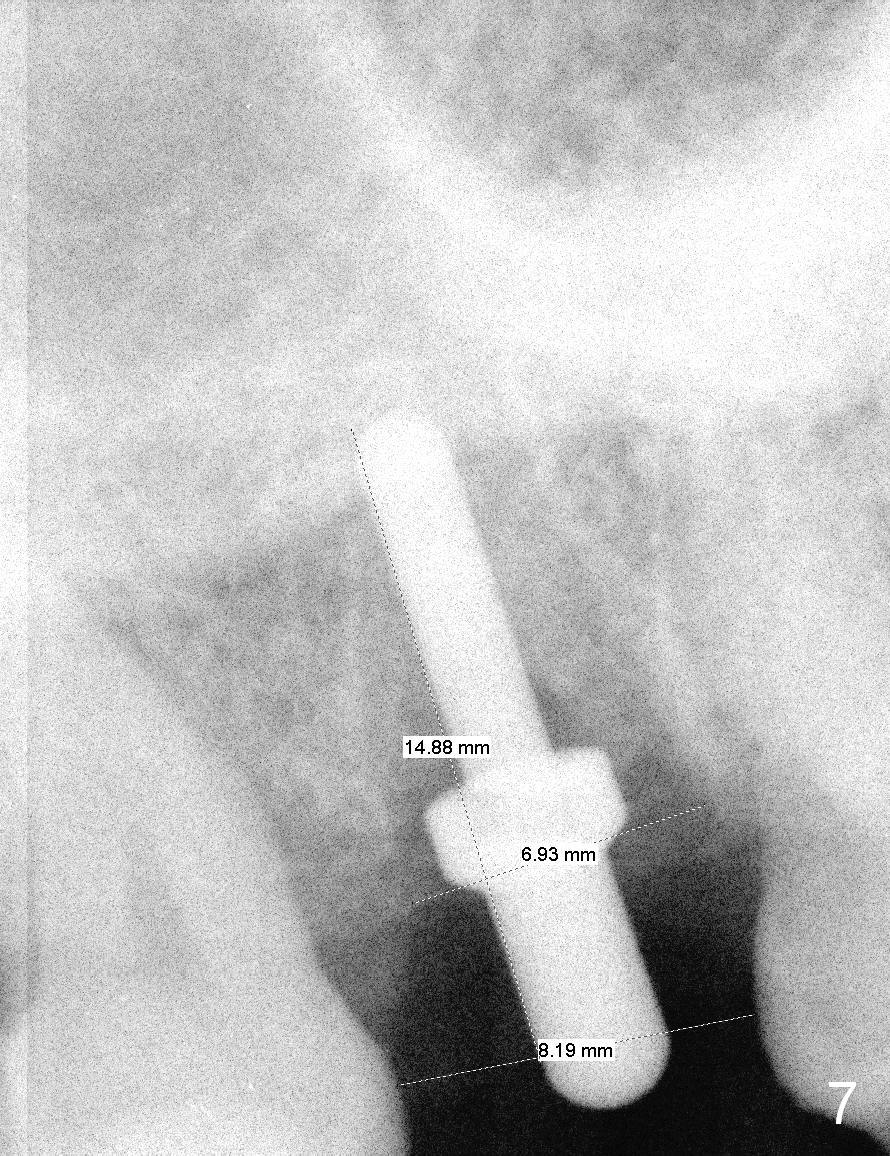

Osteotomy for immediate implant is initiated with a 2 mm pilot drill (Fig.6b red arrow) in the coronal end of the buccal slope of the septum (center of the socket). Once the drill gets initial penetration, the trajectory changes to the long axis of the tooth (Fig.6c). Then PA is taken with a parallel pin (Fig.7). It appears that the depth is not enough; there is bone apical to the pin. As osteotomy increases in diameter, burs may be deviated buccally due to the septal buccal slope (to be discussed below). With longer osteotomy, the deviation may be less. Osteotomy is deepened (Fig.6d). From this moment on, nose blowing test is done after each step. The result is all negative. As drill diameter increases, they do deviate buccally (Fig.6e arrow), since there is less bone contact buccally than lingually (compare Fig.6e,f). With the same reason, smaller tapered taps (Fig.6g pink, 5 and 6 mm) tend to be mobile buccally (arrow). When a large tap (7 mm) is inserted (Fig.8), there is no buccal mobility. It appears that the tap contacts more of the buccal plate (Fig.6h), but the coronal end of the tap is buccal (Fig.6i, pink circle). At each step of osteotomy, the coronal end of a bur or tap should be pushed as lingual as possible so that the final tap is favorable for restoration (Fig.6j). Sinus lift is done (Fig.6k red circle; Fig.9 *) before placement of 7x17 mm implant (I, >60 Ncm). Since the palatal socket is not associated with implant stability, it is closed by collagen plug (Fig.6l, blue area). As extra precaution, bone graft is placed around the coronal portion of the tissue-level implant (Fig.6l red circles), followed by collagen dressing.